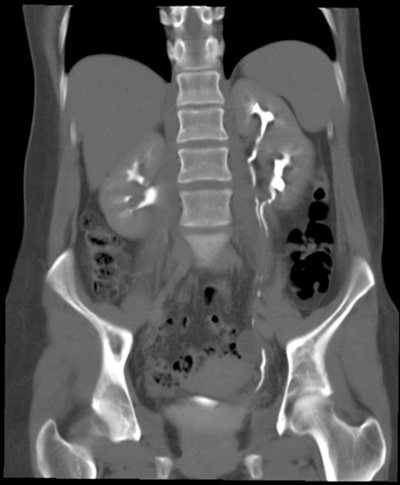

Left duplex kidney / collecting system.

One case in 125. Incomplete - common, rarely clinically significant. Complete - rare, often clinically significant.

The Weigert-Meyer law states the upper pole moiety ureter drains infero-medial to the normal lower moiety ureter.

Ureterocoele, reflux in the lower moiety, obstruction in the upper moiety (usually due to ureterocoele), PUJ obstruction, ectopic ureters.